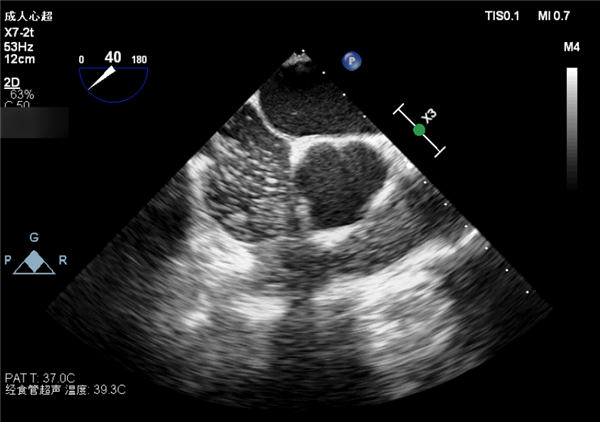

在对张女士做心脏检查时,恰逢我院超声科引进了新项目——经食管超声心动图检查项目。与普通的胸部超声相比,经食道超声心动图是将一个类似胃镜一样的超声探头从口腔经食道放置心脏后方的左心房附近,从心脏后方观察心脏内部病变,避免了胸壁和肺气等因素的干扰,图像质量明显高于胸部超声,效果更好,被誉为探查心脏的“火眼金睛”。

在了解了张女士的详细情况并对其心功能进行评估后,超声科专家为其确定了检查方案。超声医学科和神经内科医护人员协同配合,专家王彩荣主任医师亲自为其实施经食道超声心动图检查。神经内科护士长乔红艳以及其他医护人员辅助安慰患者,两科室默契配合,完美互动,成功为患者实施经食道超声心动图检查,整个过程用时不到5分钟,同时进行的发泡实验可检查患者是否存在因心脏卵圆孔未闭的不明原因脑梗死,检查中患者血压平稳,检查后无明显不适。

超声科主任何欣介绍说,经食道超声心动图检查主要是针对一些可能存在心血管病变的患者,这位患者也是为了查找脑梗的病因是否与心脏病变有关,经食管超声心动图检查,可发现冠脉病变、心脏内肿物以及血栓的形成,先心病、主动脉瓣疾病、瓣膜病等;对人工瓣膜置换术后期的功能评价和判断感染性心内膜炎的赘生物,发现瓣叶破坏以及脓肿形成,优于经胸检查;对心脏及非心脏手术的术中监护有很大作用,具有安全性高、时间短、准确度高等优点。